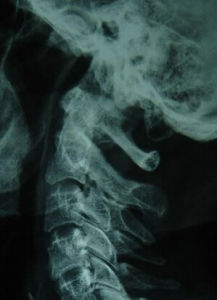

臨床表現

缺血性肌攣縮早期主要臨床表現為"5P",即Pain(疼痛),Paresthsia(感覺異常),Paralysis(麻痹),Pulseless(無脈),Pale(蒼白)。晚期形成典型的爪狀畸形。